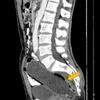

A vítima teria começado a passar mal e precisou ser levada para o hospital por seus familiares. No entanto, por vergonha, não relatou que estava com o objeto na região anal. Dias depois, sua barriga começou a apresentar um grande inchaço e um raio-x revelou o copo no reto. O homem foi internado e passou por uma cirurgia para remover o utensílio.